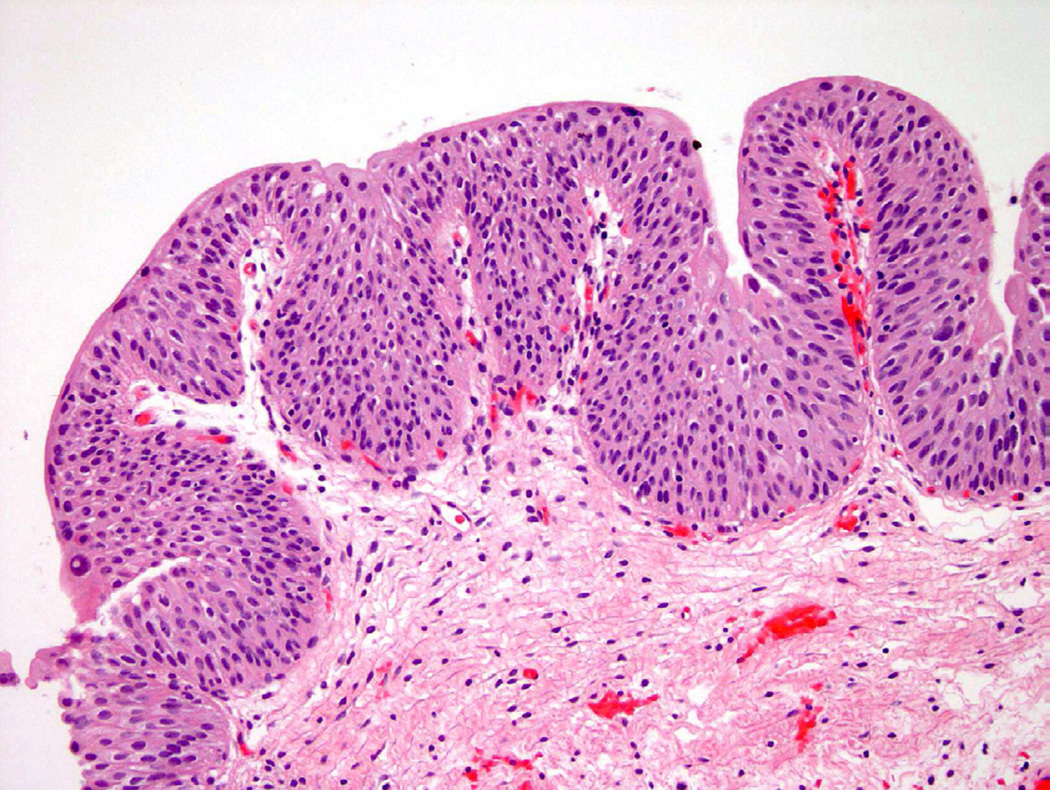

Papillary urothelial hyperplasia appears histologically as undulating epithelial thickening devoid of significant cellular atypia (Fig. 9). These papillary fronds may contain small, dilated vessels that appear as rudimentary vascular cores, but lack the branching or more complex architecture that would place this into a papillary neoplastic category18. Similar to flat hyperplasia, mild cytologic changes in the background of inflammation and instrumentation are permitted. Any indication that the atypical features are disproportional given the clinical setting, should guide the pathologist to consider a pre-neoplastic process and thus a diagnosis of “papillary hyperplasia with dysplasia”19. Taylor et al. examined 16 cases of papillary hyperplasia and were unable to definitively determine if papillary hyperplasia, with no evidence of atypia, would progress to neoplasia without intervention. Furthermore, the authors postulated that diagnosing papillary hyperplasia in a patient with a history of urothelial neoplasia likely represented a recurrence18. Conversely, papillary hyperplasia with atypical features, dysplasia, or focal CIS may predispose the patient to increased risk for disease progression19.

Figure 9.

Papillary hyperplasia shows upward tenting of vessels, suggesting a possible early papillary lesion in some instances.